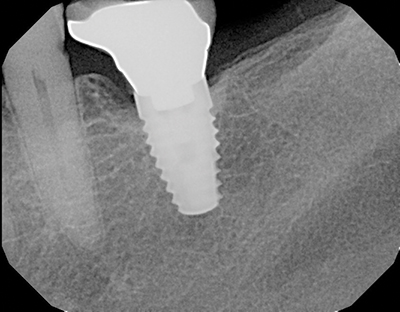

Peri-implantitis has been defined as an inflammatory process that affects the tissues around an osseointegrated implant in function and, like periodontitis, results in loss of supporting bone6 (Figs. 3 and 3a). The prevalence of peri-implantitis has been shown in some studies to range from 11% to as high as 47% of implant sites analyzed.(16) Most literature reviews agree that once bone loss has occurred around an implant, nonsurgical therapy is not as effective as surgical treatment.(17) Surgical intervention by the dentist or specialist includes raising a full thickness flap around the affected dental implant in order to completely expose the dental implant surface (Fig. 4). Mechanical debridement with hand and high-speed instrumentation as well as irrigation with various medicaments is advocated in order to detoxify the implant surface and alleviate bacterial contamination. After decontamination, the flap can be apically or coronally positioned. In addition, various regenerative technologies, including bone and soft-tissue grafts, growth factors, and barrier membranes have been used to rebuild lost tissue support around the dental implant (Figs. 5 and 5a). Different methods of guided bone regeneration around implants affected with peri-implantitis were demonstrated, and the results have been shown to be stable for a follow-up period of up to seven years.(18) That being said, no gold standard of peri-implant disease has been documented and "available evidence does not allow specific recommendations for the therapy of peri-implantitis."(19)